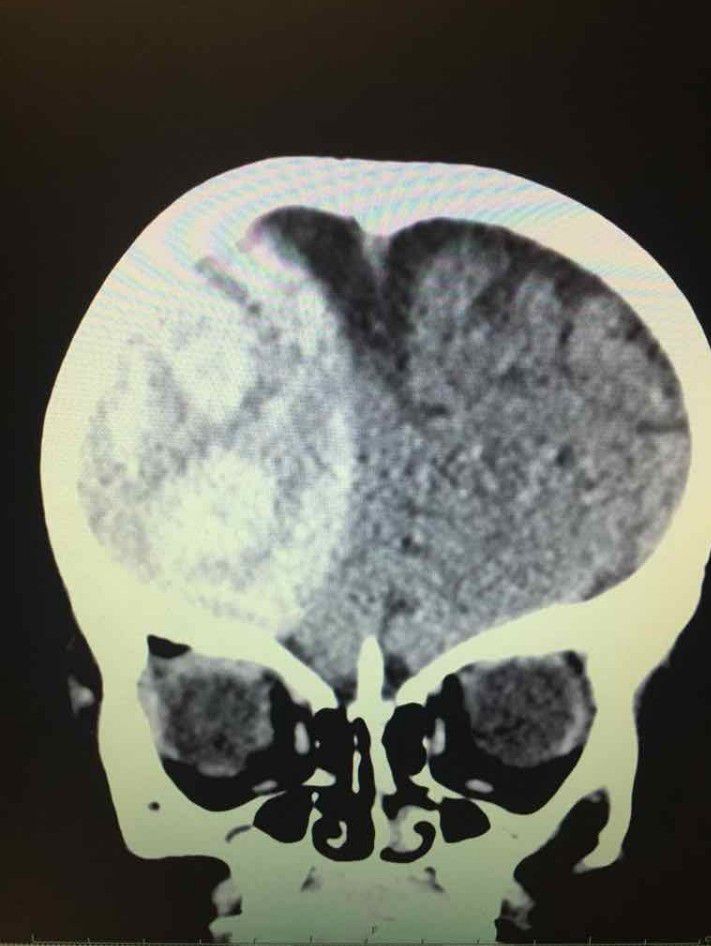

Neurosurgery